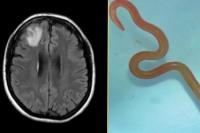

Kasus medis langka di Australia, cacing ular yang belum pernah menginfeksi manusia ditemukan hidup di otak seorang wanita